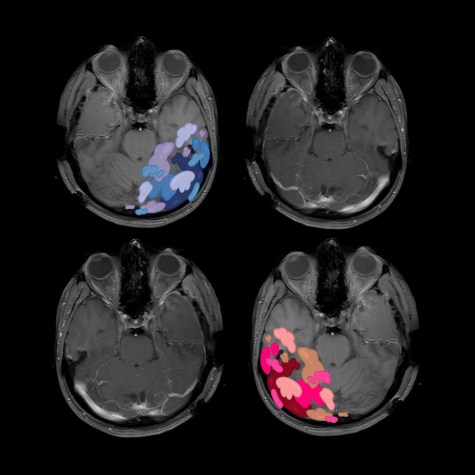

follow. In the waiting room, the doctor perches on the edge of his chair and leans forward. The tumors are glioblastoma multiforme, he tells us. They are not self-contained; they send out tendrils that snake into the crevices of the brain. The largest tumor, deep, inaccessible, and life threatening, is in the left ventricle, through which cerebral spinal fluid created to cushion the brain must pass to enter the spinal cord. They won’t know whether it, or the others, are malignant until they do a biopsy, which can’t be done until Jackie’s situation stabilizes. Meanwhile, she must have a shunt implanted to relieve the pressure in her brain.